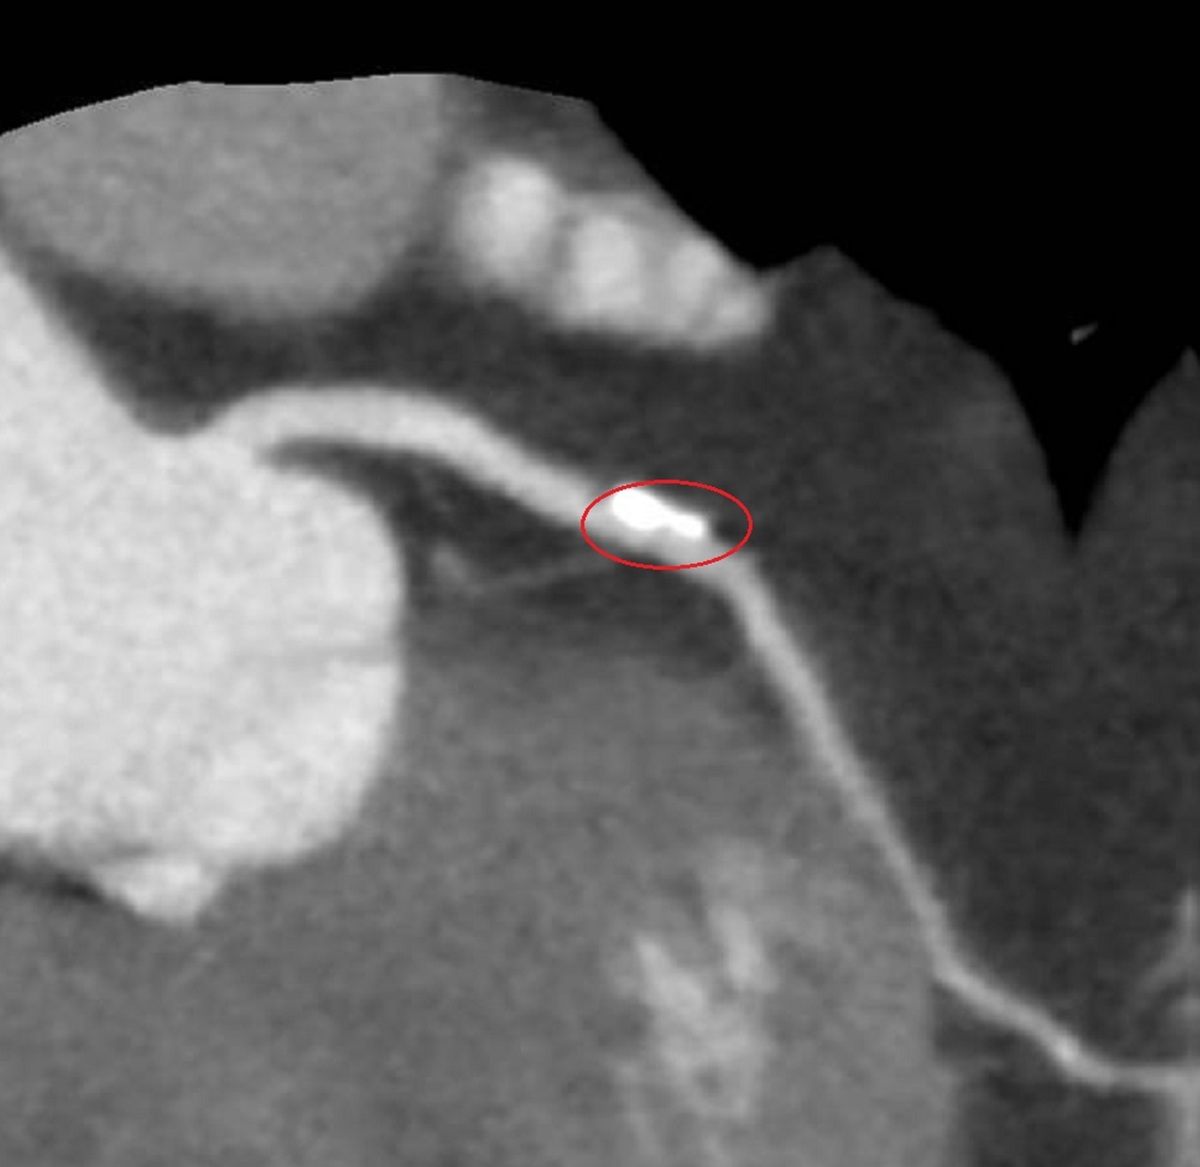

▲70歲盧女士胸悶不適,經檢查發現其心臟冠狀動脈有一處約70%阻塞,且伴隨心肌缺血與血管鈣化。(圖/彰化醫院提供)

李學林說,運動心電圖發現盧女士心血管缺血,電腦斷層發現左冠狀動脈的左前降支有一處約70%阻塞並鈣化,與病人共同決策,採IVL處理鈣化斑塊,再植入生物適應性支架,預期可達到最佳治療效果。

▲生物適應性支架融合了藥物塗層與可分解結構,植入後立即撐開狹窄血管並釋放藥物,降低再狹窄風險。(圖/彰化醫院提供)